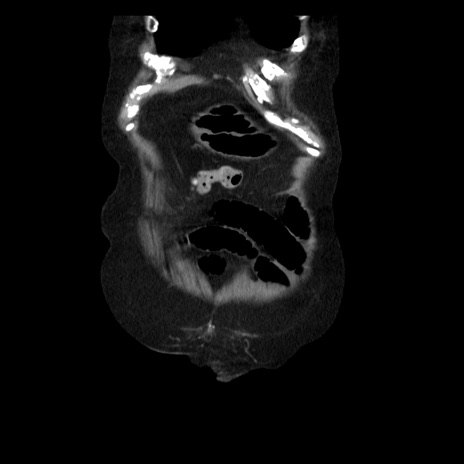

横断像